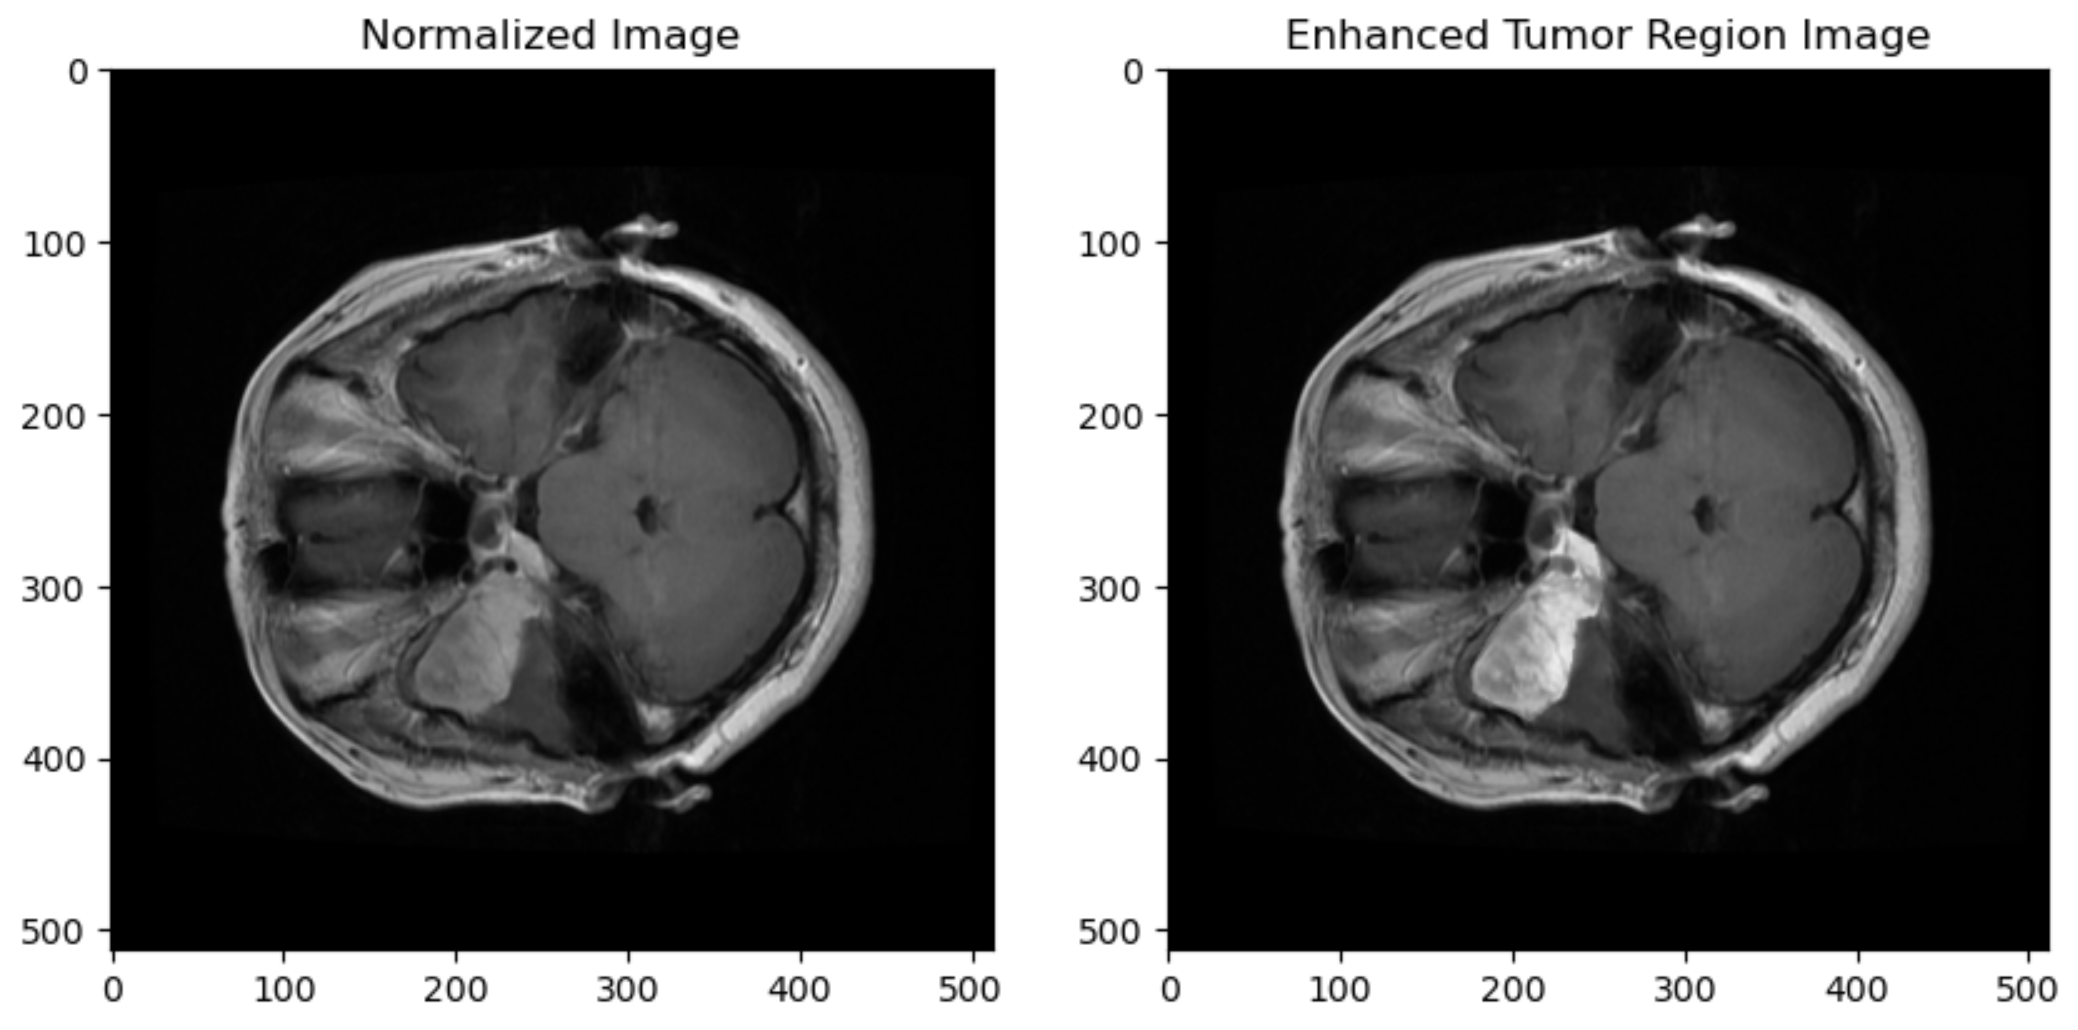

The success of both teachers and student models hinges on data preprocessing, as it unlocks rich brain image features for effective training. For this reason, all tumor images were normalized, reshaped and finally enhanced using Contrast-Limited Adaptive Histogram Equalization (CLAHE) technique [15]. Consequently, the tumor region (tumor mask) in each image is enhanced, allowing the models to extract specific tumor regions much more efficiently. Figure 3 demonstrates the difference between a normalized image without enhancement and an enhanced image before reshaping. All tumor images were of shape 512 × 512. FedBrain-Distill reshapes all images into 224 × 224 × 3. The reason behind this was that the teacher model’s input layer only accepts the latter shape since the VGGNet16 is the chosen model to be used on all teachers.

Figure 3: Comparison of normalized and enhanced tumor image before and after applying CLAHE technique.